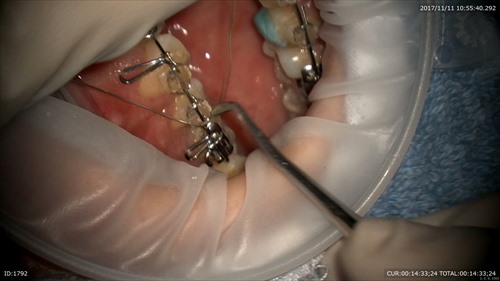

2ケース目:神経保護の治療

食事や飲み物でしみていたとの事です。むし歯を放置しているとこのように神経まで進行します。

歯科ドックを行っていたお陰でここまでのむし歯と事前にわかっていました。

MTAセメントで神経保護を行って本日は無痛で終了。

このように神経を残す事は歯の寿命が倍に伸びるという報告より

当院では事前に

歯科ドック(むし歯の進行状況と治療材料の準備のため)そしてマイクロスコープによる無痛、精密治療を行っております。そして1ケース目をご覧の通り矯正治療にも精密さが大切です。